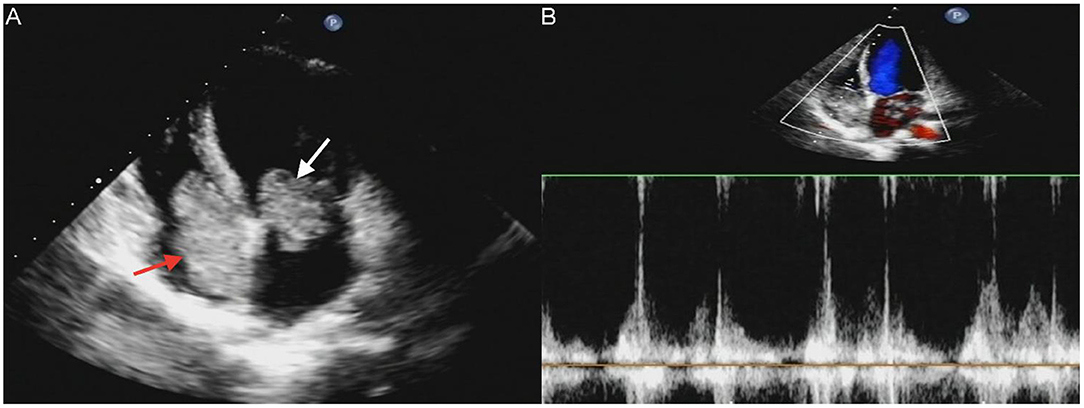

A 17-year-old girl presented to our hospital on August 22, 2021 with clouding of consciousness for more than 3 days. At 3+days prior, the patient was unable to speak the patient was unable to speak when called softly and unable to open the right eye, combined with involuntary movements of the limbs and incontinence. The patient visited the local hospital immediately, where relevant tests were performed, suggesting intracranial lesions. Since the specific treatment measures were unavailable at the previous hospital, she was transferred to our hospital for further treatment. There was no history of trauma or familial genetic diseases, such as high blood pressure and diabetes. Physical examination revealed a body temperature of 37.0°C, heart rate of 110 bpm, regular heart rhythm, blood pressure of 113/77 mmHg, and no pathological murmurs in the valve region; pulmonary auscultation revealed coarse rales in the entire lung. The pupils were equal, round, and pupillary light reflexes were delayed. Both lower limbs exhibited hypertonia and hyperreflexia of the knee and tendon reflexes. Laboratory examinations revealed the following levels (normal range): coagulation function test showed D-dimer was 0.57 mg/L (< 0.5 mg/L) and fibrinogen was 5.82 g/L (2.00–4.00 g/L). Routine blood tests showed that the absolute value of neutrophils was 7.38 × 109/L (1.8 × 109/L−6.3 × 109/L). Infection-related markers showed that the hypersensitive C-reactive protein level was 111.563 mg/L (0.068–8.200 mg/L). Creatine kinase, α-hydroxybutyrate dehydrogenase, and lactate dehydrogenase levels were 148 U/L (26–140 U/L), 218 U/L (90–180 U/L), and 295 U/L (140–271 U/L), respectively. Computed tomography pulmonary angiography (CTPA) detected filling defects in the right atrium, left atrium, and left lower pulmonary basilar artery (Figure 1), and a diagnosis of Pulmonary embolism was made. Transthoracic echocardiography (TTE) revealed irregular iso-echoic masses in the bilateral atrium that were likely myxomas, given their location and appearance in a young patient; the myxoma in the left atrium measured approximately 38 × 21 mm, and it was attached to the junction of the lower part of the interatrial septum (IAS) and the root of the anterior mitral leaflet; in the right atrium it measured approximately 51 × 27 mm, and it was attached to the lower part of the IAS (Figure 2A). These masses resulted in the acceleration of the tricuspid valve antegrade flow (Figure 2B). Craniocerebral computed tomography (CT) showed extensive hypodensity in the bilateral parts of the pons and patchy hypodensity in the left corona radiata area and bilateral basal ganglia areas. Magnetic resonance imaging (MRI) also revealed extensive hypointensity on T1-weighted imaging and hyperintensity on T2-weighted imaging in the bilateral parts of the pons, and a patchy hyperintensity on T2-weighted imaging in the bilateral basal ganglia areas; bilateral centrum semiovale; and right frontoparietal lobe, which presented as high signal on diffusion-weighted imaging (DWI) (Figure 3). This confirmed the diagnosis of brain ischemia. To prevent thrombosis, low molecular weight heparin calcium (subcutaneous injection, 0.4 ml/12 h) was commenced on the second day of admission and continued until discharge. The patient underwent successful removal surgery for a biatrial myxoma. The masses were sent for histological examination, which confirmed the presence of a myxomatous matrix containing myxoma cells (Figure 4). The patient recovered uneventfully and was discharged 9 days after the procedure. The patient has been followed-up postoperatively for over 2.5 months, and limb motor function of the patient has recovered to some degree, but there is intellectual and cognitive decline.

Figure 2. Transthoracic echocardiography (TTE) revealed masses attached to the atrial septum in the left atrial cavity (white arrow) and the right atrial cavity (red arrow) (A). Acceleration of tricuspid valves antegrade flow (B).